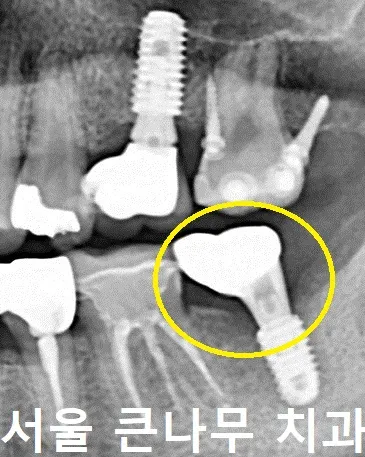

옆 사진처럼 치아를 발치한지 1년 정도 지난 상태로 내원하신 분으로 임플란트 상담을 진행하셨습니다.

처음 오셨을 때의 사진인데요, 왼쪽 아래 맨 끝 어금니의 부재로 위에 치아가 밑으로 내려와 있는 상태를 확인할 수 있습니다.

문제점을 해결하기 위해 우선 아래에 임플란트를 심었고, 위에 치아는 위로 끌어당겨주는 부분 교정에 들어가기로 하였습니다.

임플란트 식립 후 내려온 치아를 당겨주기 위한 나사(mini-implant)를 잇몸뼈에 안팎으로 심어 주었습니다.